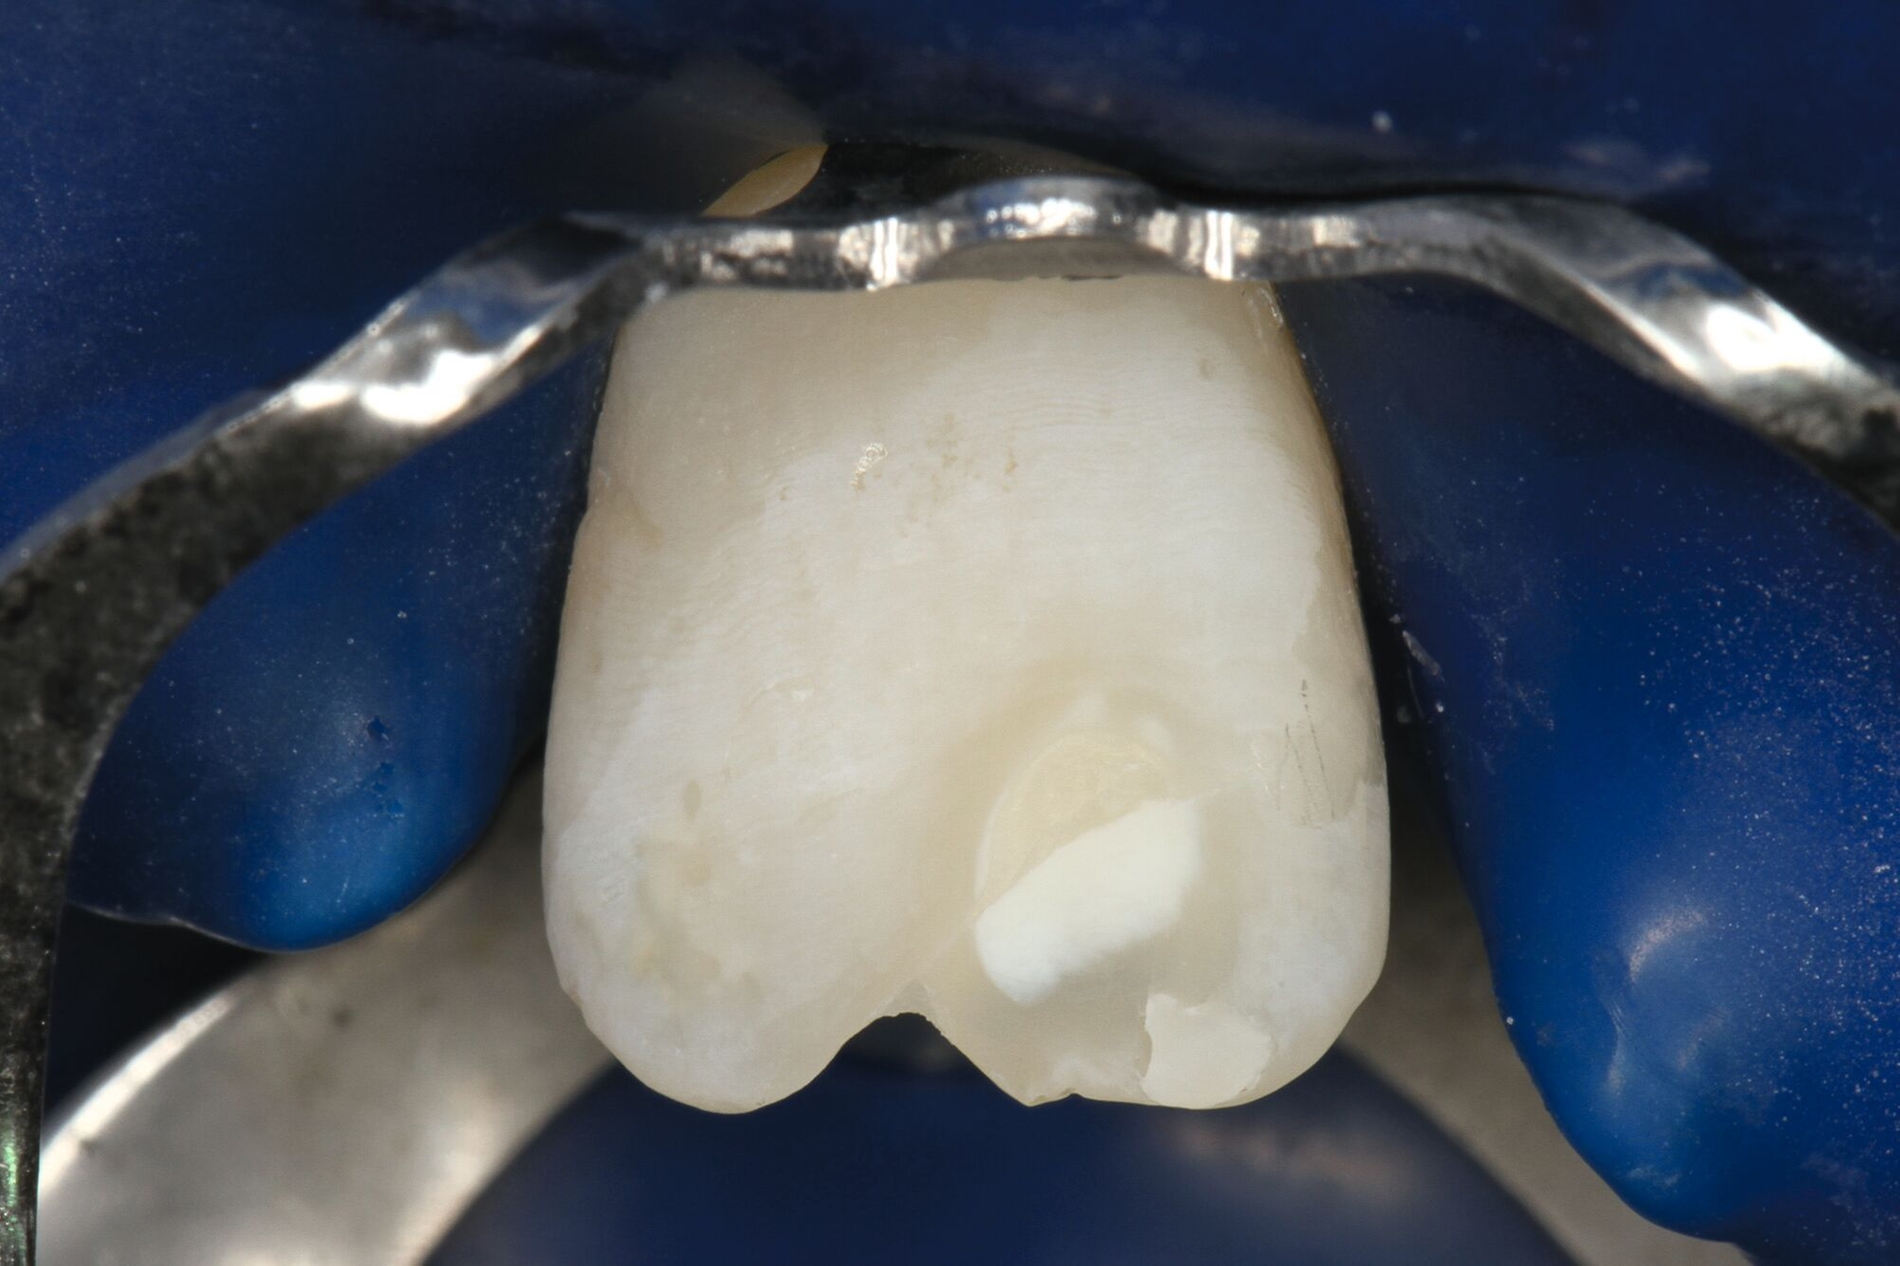

Die adhäsive Wiederbefestigung mitgebrachter Kronenfragmente bietet sich als einfache und konservative Methode zur Wiederherstellung von Funktion und Ästhetik an (Abbildung 1). Wenn das Fragment nach dem Unfall unter feuchten Bedingungen gelagert wurde, wird die Wiederbefestigung idealerweise sofort während der Notfallbehandlung durchgeführt. Wurde das Fragment jedoch durch eine längere Trockenlagerung dehydriert, sind sowohl das ästhetische Ergebnis als auch die Komposithaftung kompromittiert. In solchen Fällen wird eine Lagerung in physiologischer Kochsalzlösung oder in Wasser für einen Tag empfohlen, um eine Rehydrierung des Fragments zu ermöglichen [Farik et al., 1999], während das Dentin in der Zwischenzeit mit einem leicht entfernbaren temporären Material bedeckt ist (zum Beispiel Kalziumhydroxid-Zement). Die Rehydrierungszeit kann durch eine feuchte Lagerung des Fragments in einem sauberen Drucktopf auf 30 bis 60 Minuten verkürzt werden.

Vor der adhäsiven Befestigung sollten sowohl das Fragment wie auch der Zahn gründlich gereinigt werden. Sandstrahlen kann eine gute Option sein, um Reste von provisorischem Material zu entfernen, die während der Notfallbehandlung zur Versiegelung des Dentins aufgebracht wurden. In Bereichen mit reduzierter Restdentinstärke ist jedoch höchste Vorsicht geboten, um keine Pulpaexposition zu riskieren. Zusätzliche Präparationen wie das Abschrägen der Schmelzränder oder das Präparieren einer inneren Rille im Dentin führen zu einer verbesserten Haftung, erschweren jedoch die exakte Repositionierung des Fragments. Dennoch kann im Einzelfall, bei offensichtlichen kohäsiven Schmelzrissen im Randbereich (aufgelockerte Schmelzprismen), eine vorsichtige Randpräparation sinnvoll sein, um eine qualitativ hochwertige Adhäsivfläche zu erzielen.

Zahnoberfläche und Fragment werden mit einem Adhäsivsystem vorbehandelt, wobei eine vorherige Schmelzätzung mit Phosphorsäure unabhängig vom verwendeten Adhäsivsystem sehr zu empfehlen ist. Bei gefüllten, schichtbildenden Adhäsivsystemen würde die Polymerisation des Adhäsivs die Passung des Fragments beeinträchtigen und sollte daher unterbleiben. Universaladhäsive sind diesbezüglich im Vorteil, da sie so dünn verblasen werden, dass sich trotz Vorhärtung keine Passungsprobleme ergeben. Ein fließfähiges Komposit wird auf die Bruchflächen beider Teile aufgetragen und über die Oberfläche verteilt. Nach der Reposition des Fragments wird überschüssiges Material entfernt und die Frakturlinie von labial und palatinal lichtgehärtet. Empfohlen werden leistungsfähige Polymerisationslampen und längere Belichtungszeiten, um sicherzustellen, dass über die Zahnstruktur genügend Energie an die gesamte Klebefläche abgegeben wird. Das Kühlen des Zahnes mit Druckluft hilft, den Temperaturanstieg während der Polymerisation zu verringern und kann somit hitzebedingten Pulpaschäden vorbeugen. Kompositüberschüsse, die nach der Polymerisation im Bereich der Frakturlinie verbleiben, können einfach mit einem Skalpell entfernt und bei Bedarf poliert werden. Im Einzelfall kann bei einer geringen Klebefläche die Frakturlinie nach der adhäsiven Wiederbefestigung hohlkehlartig ausgeschliffen und anschließend mit Komposit aufgefüllt werden.